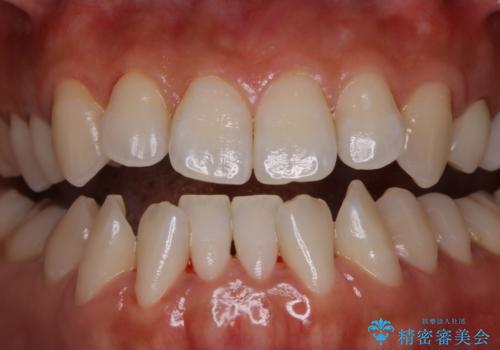

矯正治療が終わったタイミングでPMTC

担当医 歯科衛生士